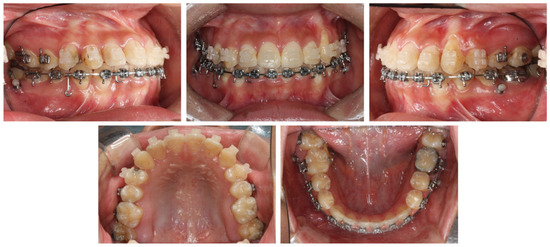

2.4. Treatment Progress